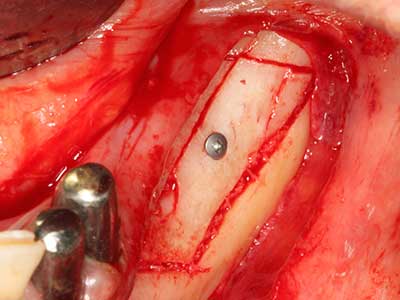

En la extracción de bloques óseos la piezocirugía también presenta ventajas adicionales: Además de la alta precisión en la osteotomía que ya se ha descrito antes, se ha comprobado que el uso de los delgados insertos de sierra resulta especialmente cuidadosas con el hueso. Frente a esto, sobre todo cuando se usan las fresas de Lindemann, cabe esperar pérdidas en la extracción significativamente más altas debido al mayor grosor de la parte frontal del cabezal (Lakshmiganthan, Gokulanathan et al. 2012). La separación basal que se necesita en particular en los injertos de bloque extraídos de forma retromolar se ve facilitada mediante sierras perpendiculares especialmente previstas a tal fin, lo que permite considerar que la cirugía piezoeléctrica es un procedimiento preciso y seguro para la obtención de bloques de hueso en el área retromolar (Happe 2007) (fig. 1-12).